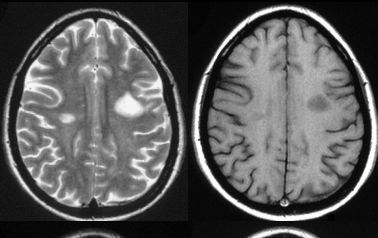

Alors l'avantage en T2 c'est que tout est visible y compris les lésions, et souvent tu as de l'eau accumulé ou encore une hypervascularisation au niveau de ces lésions, et comme tu sais le liquide a un T2 long, donc est hyper intense en image IRM. C'est donc pour cela que en T1 les lésions sont hypo intenses, on utilise le T1 pour les lésions surtout pour savoir si la lésion est encore active ou pas ( culture g ).

Tiens ici tu vas voir une lésion en T1 et en T2 pour être sur de ne pas oublié !!

T2                                             T1